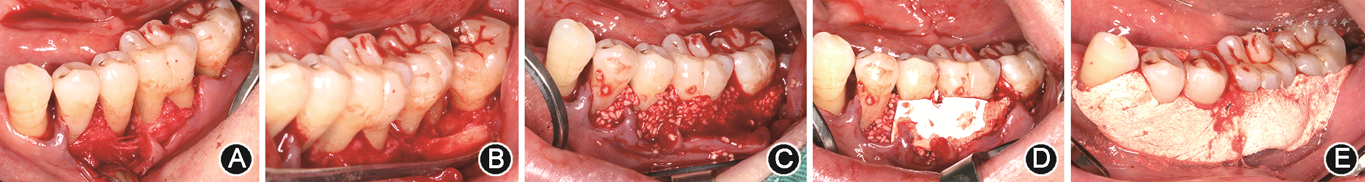

牙周组织再生性手术治疗即通过翻瓣手术清除根面结石及肉芽组织,随后在根分叉区域填入自体骨或人工骨制品,可同期附加生物屏障膜,以促进牙周组织再生的治疗(图5)。

再生性手术治疗是根分叉病变的理想治疗方法[20],但其适用范围非常有限。一般用于下颌磨牙Glickman Ⅱ度根分叉病变以及上颌磨牙颊侧Glickman Ⅱ度根分叉病变。Glickman Ⅲ度根分叉病变以及上颌磨牙邻面Glickman Ⅱ度根分叉病变均不适合行再生性手术治疗。上文提及下颌磨牙Glickman Ⅱ度根分叉病变也可采用隧道成形术,因此,对于下颌磨牙Glickman Ⅱ度根分叉病变,治疗选择需根据临床检查进一步考量。临床检查需关注颊侧和舌侧是否均存在Glickman Ⅱ度根分叉病变。此外,还需关注牙龈软组织及牙体组织的解剖特征,判断牙龈能否充分覆盖根分叉入口。当下颌磨牙颊侧及舌侧均存在Ⅱ度根分叉病变时,再生性手术治疗的效果难以预测。相比之下,隧道成形术常为首选方案。对于骨质破坏较多、牙龈退缩、术后牙龈难以覆盖根分叉的下颌磨牙单侧Glickman Ⅱ度根分叉病变,再生性手术治疗难以开展,此时也可考虑采用隧道成形术。对于骨质破坏不多、牙龈能充分覆盖根分叉入口的下颌磨牙单侧Ⅱ度根分叉病变,可考虑采用再生性手术治疗。